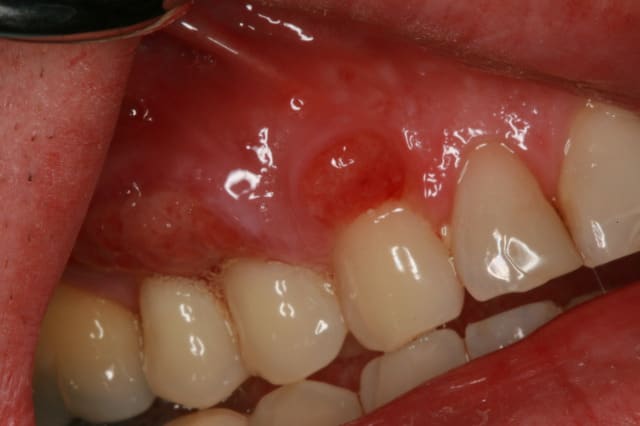

A la vue de ta photo on peut comprendre que tu as choisi de faire une tunnelisation. En ayant fait plusieurs dizaines et pu les comparer avec les lambeaux déplacés coronairement traditionnels ou modifiés, je ne suis pas sûr que le résultat esthétique soit meilleur : je n'aime pas la partie exposée du greffon conjonctif qui a esthetiquement souvent du mal a s'intégrer harmonieusement dans le contexte gingival du site receveur.

En post op, le lambeau tunnel revouvrait entièrement le greffon, Je crois que l'épaisseur du greffon a favorisé une nécrose de surface du lambeau, de plus quelques points ont cédées avant le contrôle de 2 semaines

Combien l'épaisseur de ton greffon ?

Nécrose de surface ? il était si mince ton lambeau, c'est étrange, jamais vu cela après des dizaines de tunnels.

Mes greffons font en moyenne environ 1.27 à 1.61 mm